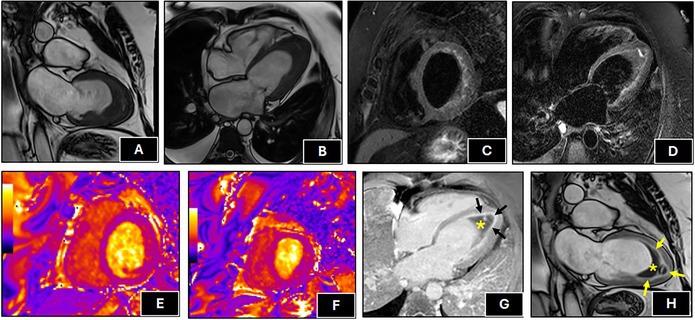

Clinical Images: Löffler endocarditis: a rare cardiac manifestation of eosinophilic granulomatosis with polyangiitis.